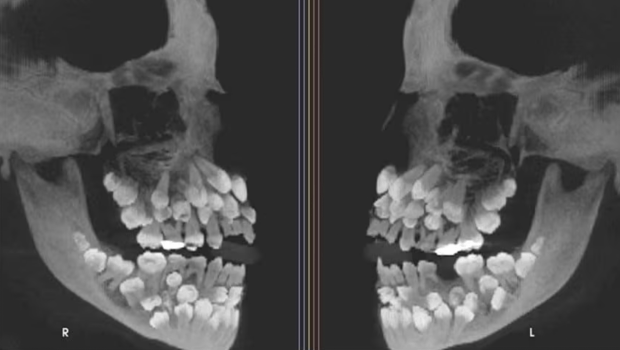

巴西一名11歲女童被發(fā)現(xiàn)口內(nèi)有81顆牙,包括18顆乳牙、32顆恒牙及31顆多生牙(supernumerary teeth),遠(yuǎn)超成人正常32顆恒牙的數(shù)量。此病例于《美國正畸與牙面骨科雜志》中發(fā)表,引起全球?qū)W界關(guān)注。

▲巴西一名11歲女童被發(fā)現(xiàn)口內(nèi)有81顆牙,包括18顆乳牙、32顆恒牙及31顆多生牙(supernumerary teeth)。《美國正畸與牙面骨科雜志》

這名11歲女童因需拔除一顆上頜乳牙而前往朱伊斯迪福拉聯(lián)邦大學(xué)牙科醫(yī)院就診,當(dāng)時(shí)臨床檢查并未發(fā)現(xiàn)明顯異常,但X光檢查結(jié)果令人瞠目結(jié)舌,因揭示其口內(nèi)共有81顆牙,其后證實(shí)女童患有多牙癥。研究團(tuán)隊(duì)進(jìn)一步使用錐形束計(jì)算機(jī)斷層掃描(CBCT)確認(rèn)牙齒的精確位置及形態(tài),發(fā)現(xiàn)多生牙分布于牙弓各處,部分深埋于牙齦內(nèi),形態(tài)異常,難以與正常牙齒區(qū)分。